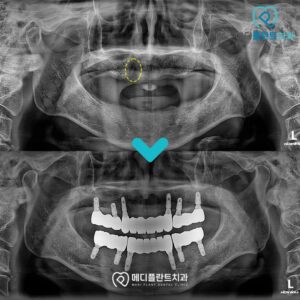

춘천수면치과, 임플란트 치료 과정이 두려워 미루고 있다면 . 안녕하세요 🙂 춘천수면치과 메디플란트치과입니다. . 치아에 문제가 생겨 불편하다면 일상생활에 큰 어려움이 발생할 수 있습니다. . 양치 자체도 불편하고 어렵기 때문에 치주…